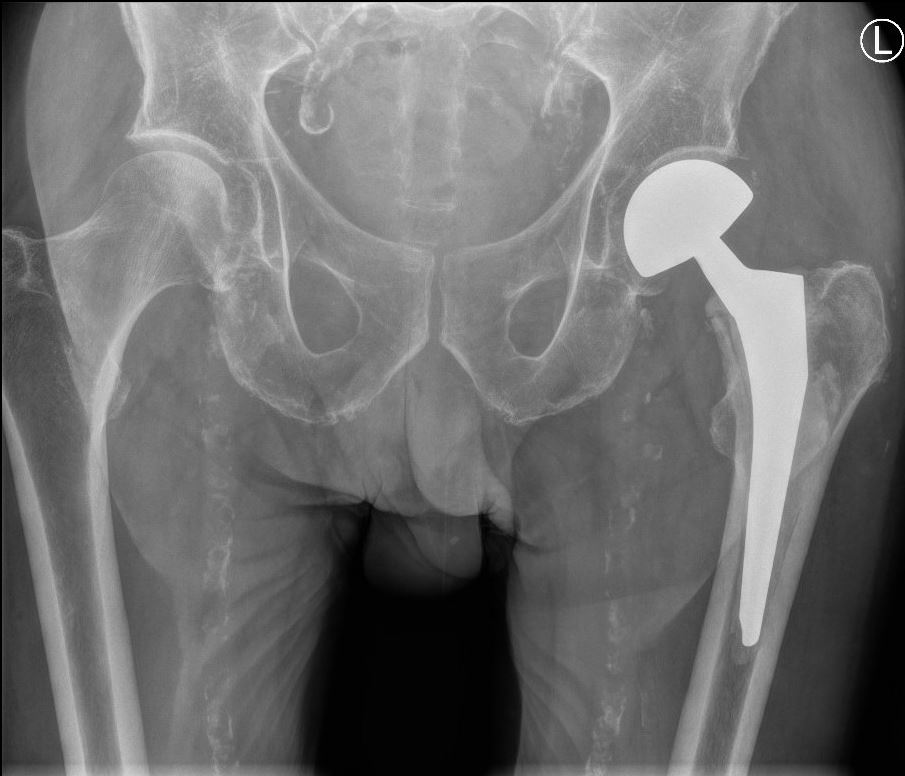

Operatie: in de meerderheid van de gevallen is er een indicatie voor operatie. Het doel van de operatie is de patiënt pijnvrij te krijgen en zo snel mogelijk weer uit bed te krijgen, aangezien patiënten snel zieker worden als ze alleen maar in bed kunnen blijven liggen (ontstaan van oa. longontstekingen en doorligplekken) Het soort operatie is afhankelijk van onder andere de leeftijd van de patiënt, de plaats van de breuk en de stand van de breuk. Als de breuk in de nek van de heup zit (vlak onder de kop), dan zal er gekozen worden voor het vastzetten van de heupkop met bijvoorbeeld 1 of meer stevige schroeven in de heupkop, of voor het vervangen van de heupkop met een heupprothese. Indien de breuk onder de nek en dus meer in het bovenbeen zit, zal er gekozen worden voor of een stevige schroef in een plaat, of voor een stevige schroef met een pen in het bovenbeensbot.